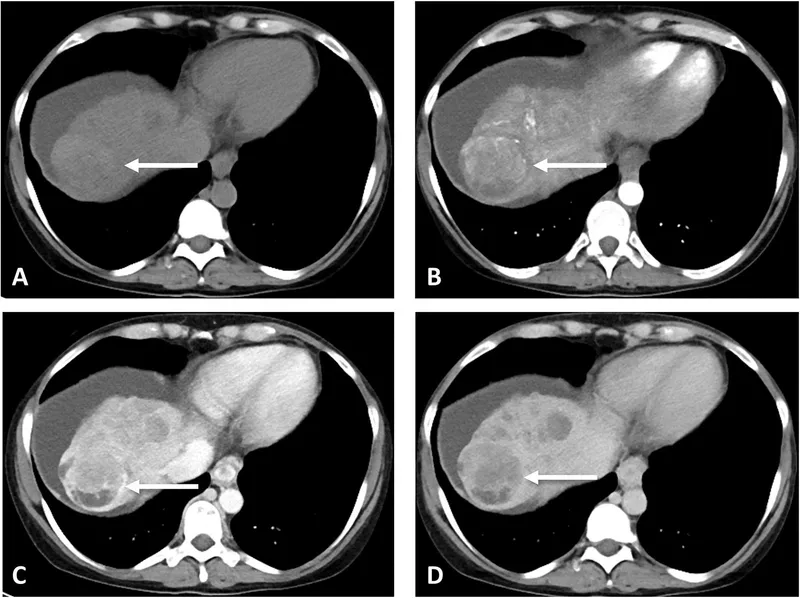

- Imaging: Multiphasic CT/MRI is key.

- Arterial phase hyperenhancement.

- Venous/delayed phase washout.

⭐ In a cirrhotic patient, classic imaging findings (arterial hyperenhancement, venous washout) are diagnostic for HCC, making a biopsy often unnecessary.

- Hallmark on imaging: arterial phase hyperenhancement and portal venous washout.